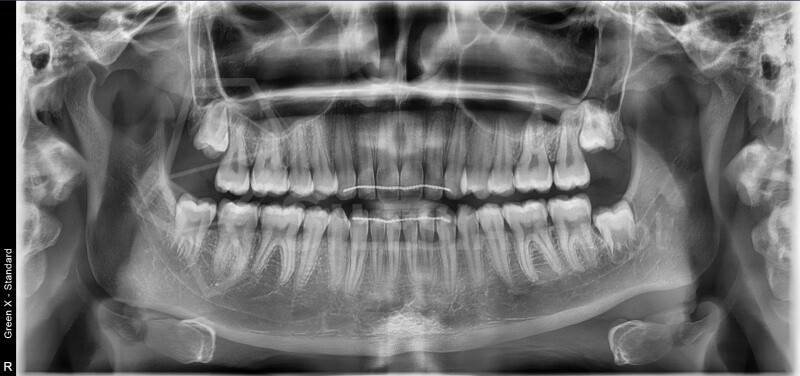

Zdjęcie panoramiczne (pantomogram) obejmuje całe uzębienie i szczęki, pokazując zmiany, których nie widać na zdjęciach punktowych RTG – takie jak torbiele, guzy, stany zapalne czy zwyrodnienia stawów.

To podstawowe badanie profilaktyczne, które warto wykonywać regularnie – przynajmniej raz na dwa lata.

• Najnowocześniejszy tomograf stożkowy w regionie – Vatech Green X (model 2025).